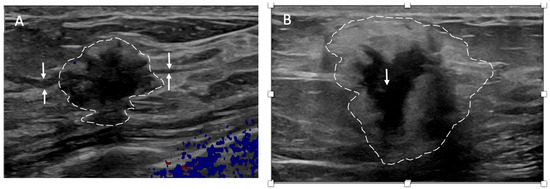

Ultrasound of the breast. Office-based cryoablation is optimized for treatment of ultrasound-visible breast cancers. Consequently, breast ultrasound should be performed of all suspicious imaging abnormalities to assess eligibility for ultrasound-guided cryoablation. Ultrasound permits assessment of the cancer’s proximity to the overlying skin and underlying chest wall and also enables detection of changes in adjacent tissue architecture (e.g., edema, tissue distortion, extension of tumor into adjacent ducts) and could indicate the presence of more extensive disease that would need to be incorporated into the treatment plan (Figure 2). Proximity (<5 mm) of a cancer to the skin is generally regarded as a contraindication to cryoablation, but a safe skin distance can sometimes be created using hydrodissection or injection of saline between the tumor and overlying dermis.

Figure 2.

(A) shows dark, dominant, irregular mass encircled by hash marks with intraductal tumor extensions (dark bands bracketed by paired arrows) extending from left and right sides of dominant mass. (B) shows dark, irregular dominant mass (arrow) surrounded by peri-tumoral edema outlined by hash marks.